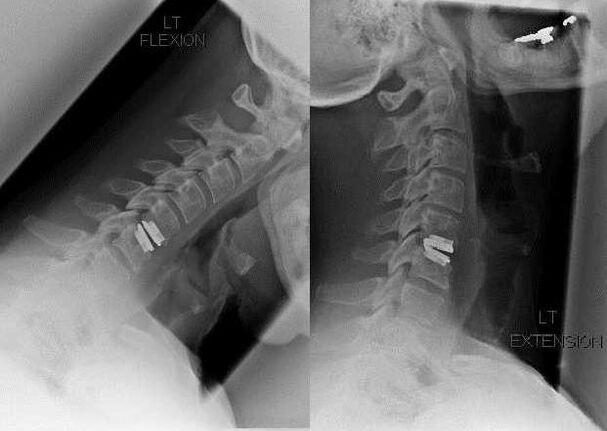

Cerrahi müdahale

Cerrahi müdahale endikasyonları konservatif tedavinin etkisizliğinin yanı sıra diskojenik miyelopati, vertebral arter sendromu ve radiküler sendrom gibi servikal osteokondrozun komplikasyonlarını içerir. Omuriliğin, kan damarlarının ve omurilik köklerinin basıncını azaltmak için aşağıdaki işlemler gerçekleştirilir:

Ameliyat sırasında kemik parçaları ve bağlar çıkarılabilir, omurlararası diskler tamamen veya kısmen çıkarılabilir. Küçük fıtık çıkıntıları için sıklıkla disk çekirdeğinin lazerle buharlaştırılması yapılır.

Vertebral yapıların eksizyonundan sonra, spinal füzyon veya kemik ve dermal otogreftlerin yerleştirilmesi nedeniyle sıklıkla omurga hareket bölümlerinin stabilizasyonu gerekir.